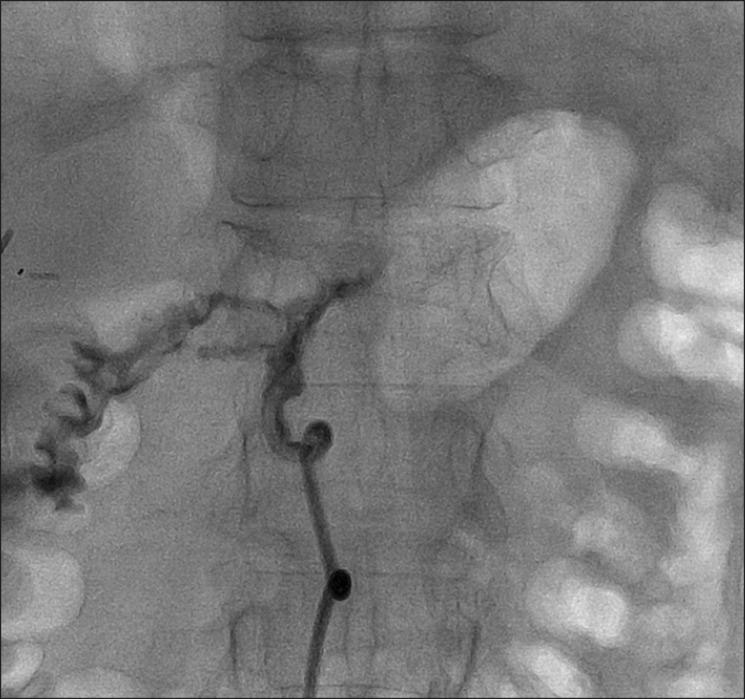

Closure of pancreatoduodenal fistula using vascular occluding coil embolization and fibrin glue injection: a case study.

The conventional management of pancreatoenteric fistulas and pancreatic abscess with aggressive surgery or percutaneous drainage catheter placement are associated with increased surgery-related morbidity and mortality, and a longer hospitalization. We report here a case of successful closing pancreatoduodenal fistula, which remained open after the percutaneous catheter drainage of pancreatic abscess, by using vascular coil embolization and fibrin glue injection. This procedure is a less invasive, more effective and better tolerated strategy for the management of pancreatoenteric fistula in a selected group of high risk patients and needs further investigation.